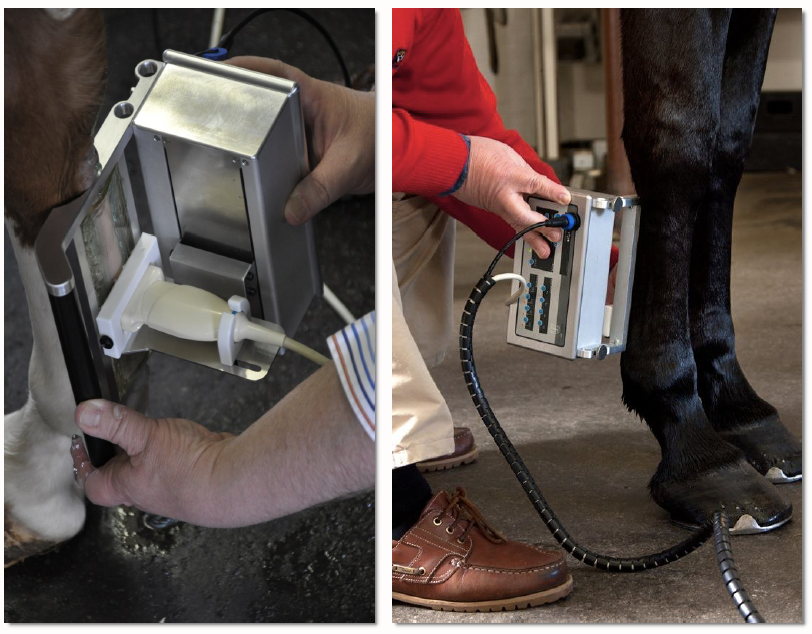

Recently, in both human and veterinary medicine, the technique of ultrasound tissue characterization, also known as UTC, has been utilized to fill in the gaps created by traditional ultrasound. In this technique, a standard ultrasound probe is placed in a motorized tracking device. This device is placed on the horse’s skin over the tendons. The probe is automatically moved along a track that allows it to uniformly scan a length of leg. A 12-centimeter length is scanned in 45 seconds. Images are captured every 0.2 millimeters. The over 600 images and information produced are digitally manipulated to generate a 3D tendon representation.